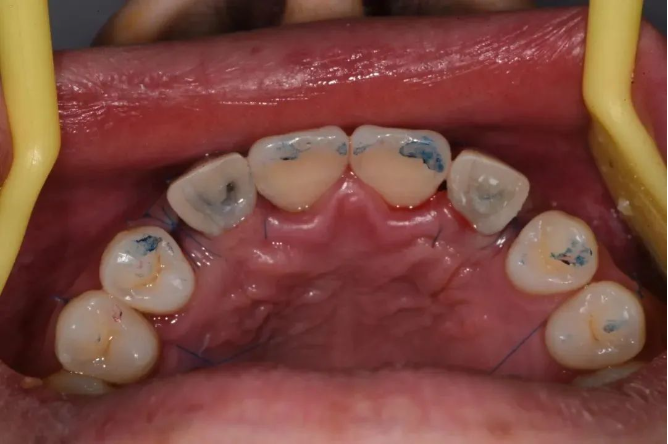

口内检查

12、13、22、23先天缺失

患者缺牙间隙偏宽,唇侧轮廓轻度塌陷,息止颌位切端暴露量正常

种植导板在口内试戴,密合性良好

颌面观显示12、22区轮廓丰满度良好

临时修复体邻接良好